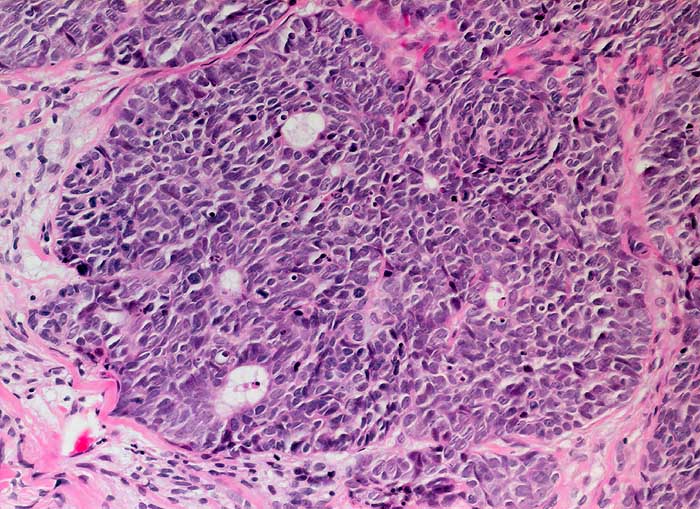

basaloides Plattenepithelkarzinom

maligner Tumor

Portio

Basaloid differenziertes Plattenepithelkarzinom. Die Tumorzellen erinnern an die Zellen eines grosszellig neuroendokrinen Karzinoms.

polypöser Tumor der Zervix

Histologie

200